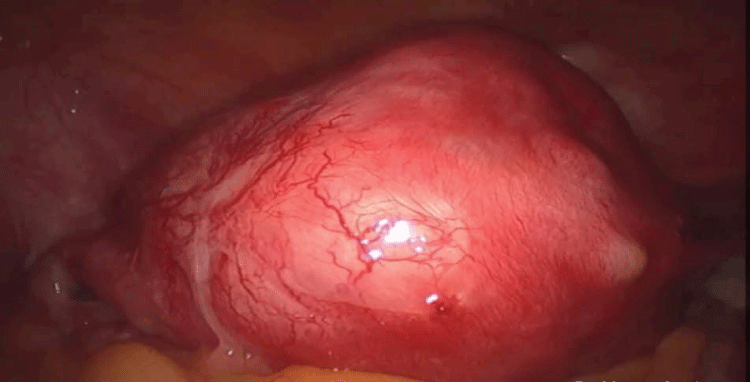

At first, it was injected into the uterine wall a vasoconstrictor agent diluted in saline solution in order to decrease bleeding during surgery. Using an ultrasonic scissor, a horizontal incision was made in the uterine fundus respecting the limits of the fallopian tubes. The incision continued along the coronal direction, however, the uterine cavity was never reached. A second incision was done, making a wide wedge-shaped resection of the anterior uterine wall and fundus. The incision was further continued along the anterior wall of the uterus. Afterward, the affected tissues were clamped with a forceps, identified and removed from the surrounding myometrium. If the myometrium appeared normal, it was spared as much as possible. The procedure was performed with caution to avoid damaging the endometrium (Figure 2 and Figure 3). The myorrhaphy was performed with interrupted sutures in two layers with polyglactin (Figure 4). The conservative procedure was concluded in 95 minutes.

On the second postoperative day the patient was discharged without pain complaint and in good clinical condition. Histopathology analysis show presence of endometrial tissue in the myometrium, confirming adenomyosis (Figure 5 and Figure 6).